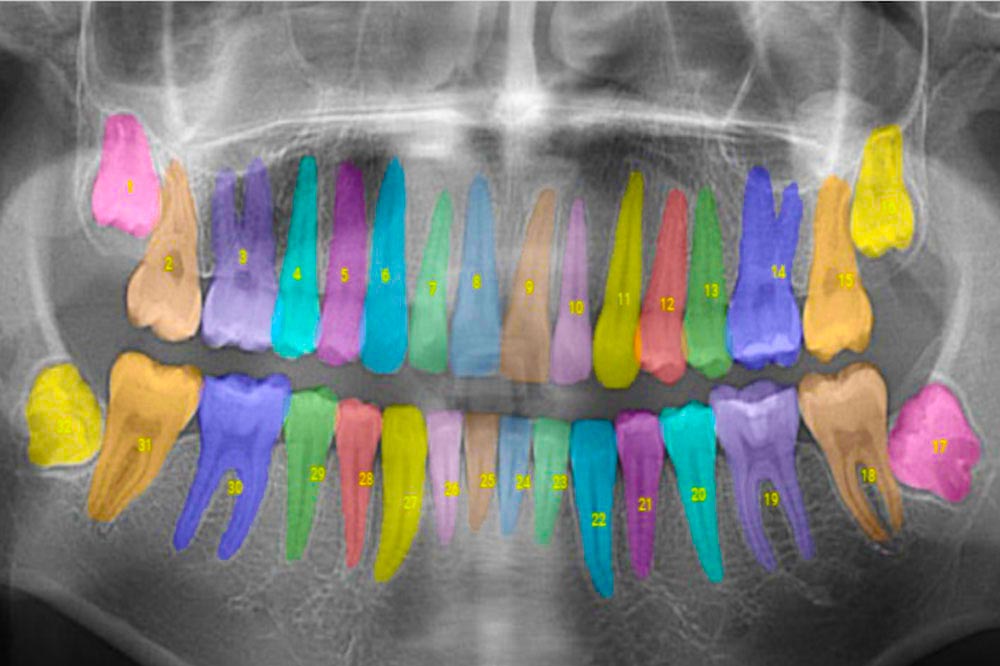

MIT alumni-founded company analyzes and annotates dental X-rays to help dentists offer more comprehensive care...The company has already analyzed tens of millions of X-rays. They are used by dental practices nationwide and are currently working with insurance companies that represent more than 75 million patients in the U.S.

Those two bottom wisdom teeth are going to cause problems.

Year ago I had two bottom wisdom teeth that looked something like that, except worse. The procedure for taking them out was quite an experience. ;)

Those are young wisdom teeth.

They grow roots and push the other teeth.

Get them out quick.

Else they mess up your other teeth, and are heck to remove.